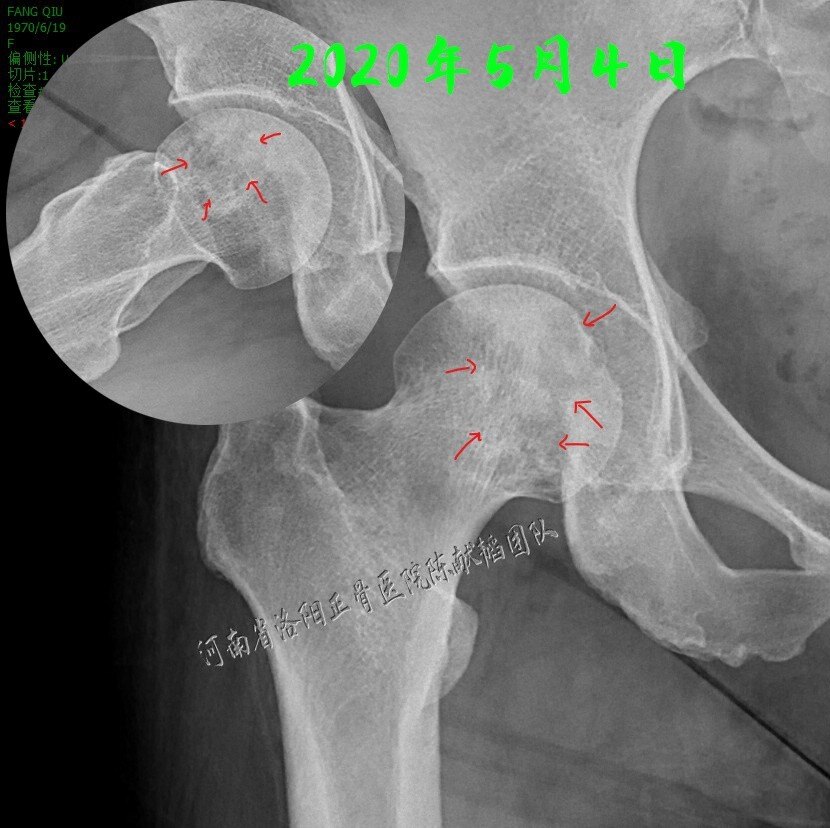

"颠倒黑白"真的吓死人,再谈股骨头坏死的影像特点